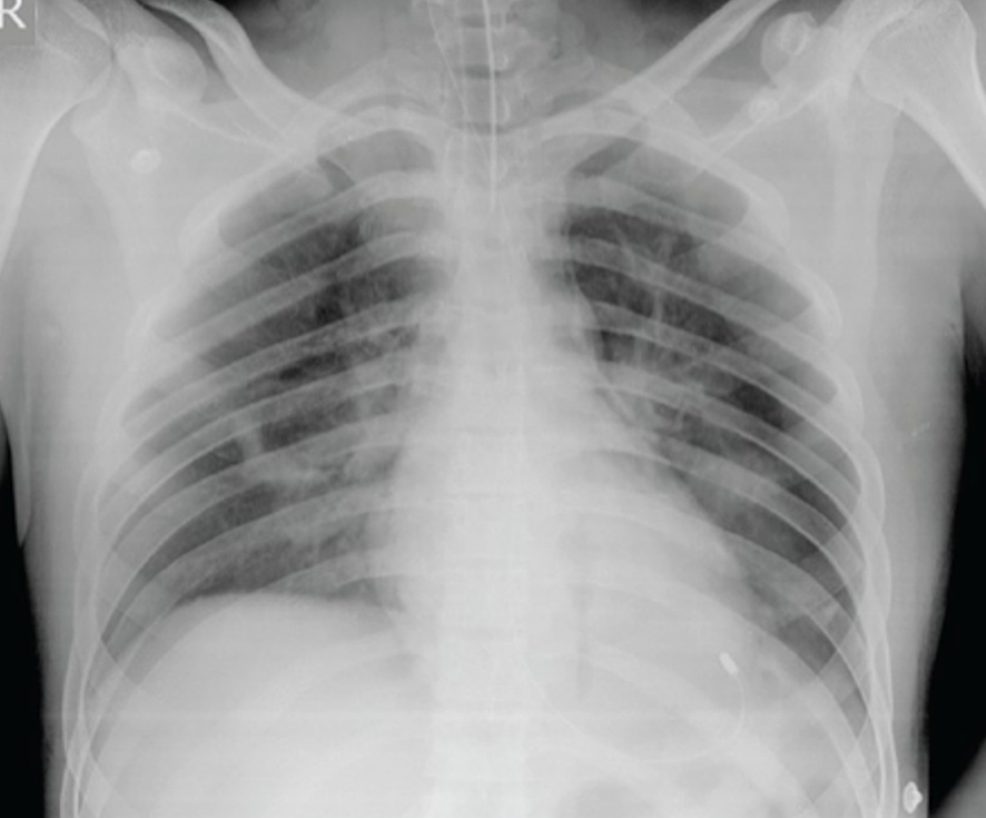

Inhalation Injury

Chemical Burns · Types, Complications, Management Burned Lungs From Fire Smoke inhalation occurs when you breathe in the heated particles and gases produced by fire. Learn about signs, symptoms, treatment, and recovery. Inhalation injury or smoke inhalation injury remains one of the leading causes of death. Chest pain can also be a sign of a heart attack. Different fires produce a different combination of these harmful substances, depending on what's.. Burned Lungs From Fire.

Inhalation Injury Burned Lungs From Fire Smoke inhalation occurs when you breathe in the heated particles and gases produced by fire. Breathing in hot air, smoke, or chemical fumes can cause irritation or swelling in your air passages. Some of these chemicals can. Learn about signs, symptoms, treatment, and recovery. Chest pain can also be a sign of a heart attack. Inhalation injury or smoke inhalation. Burned Lungs From Fire.